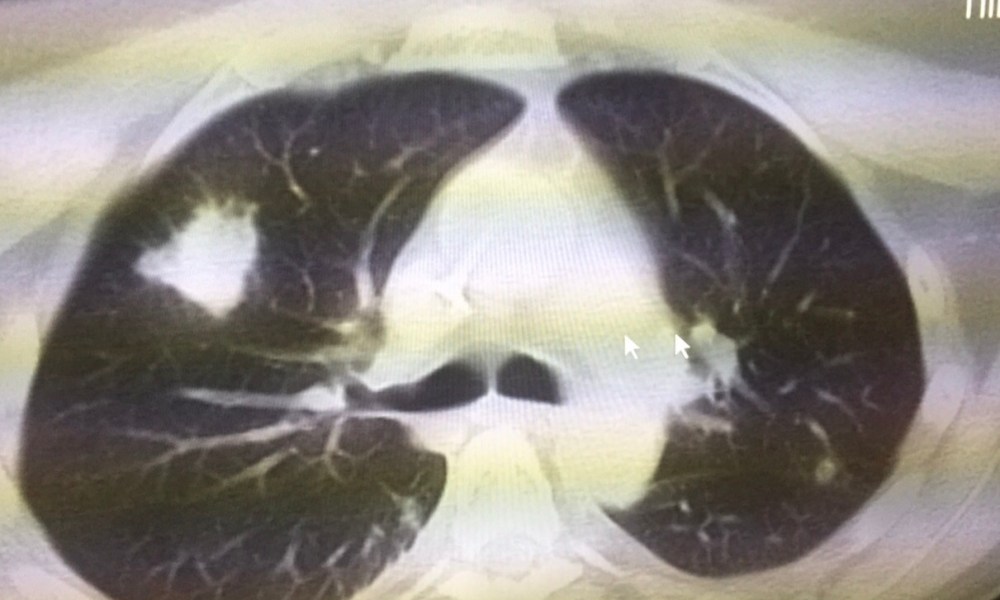

Just after engraftment, he developed fever again (absolute neutrophil count of 370 cells/cubic millimetre of blood). Septic work up was negative, and empirical piperacillin/tazobactam for 5 days did not help. A CT thorax was done, showing a solid nodule (figure). He had remained on oral posaconazole throughout the period.